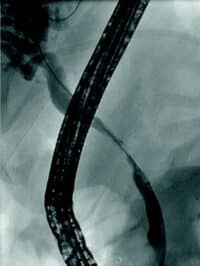

Obstruksjon av gallegang

Inflammasjon og fibrose i caput av pankreas kan skade gallegang og føre til benigne strikturer og kolestase. Slike strikturer kan være krevende å behandle. Det er viktig med god bildediagnostikk i forkant av terapi for å utelukke malign striktur, noe som kan være vanskelig på grunn av de inflammatoriske/fibrotiske forandringene sekundært til kronisk pankreatitt. Det er svært viktig at man ikke intervenerer endoskopisk dersom usikkerhet om malign etiologi men henviser til senter med HPB kirurg og MDT vurdering. Standard behandling av benigne strikturer har vært ERCP med gjentatte dilatasjoner og innleggelse av multiple plaststenter i gallegang over en periode på ett år (Fig 5). De senere år har bruk av selvekspanderende metallstent i 6-12 mnd. blitt mer vanlig dersom forholdene teknisk ligger til rette for dette. Det er imidlertid risiko for residiv av striktur på grunn av progresjon av grunntilstanden så gjentatt endoskopisk behandling kan bli nødvendig.

Fig 5: Pasient med gallegangsstriktur sekundært til kronisk pankreatitt som behandles med endoskopisk ballong dilatasjon og stenting av gallegang.